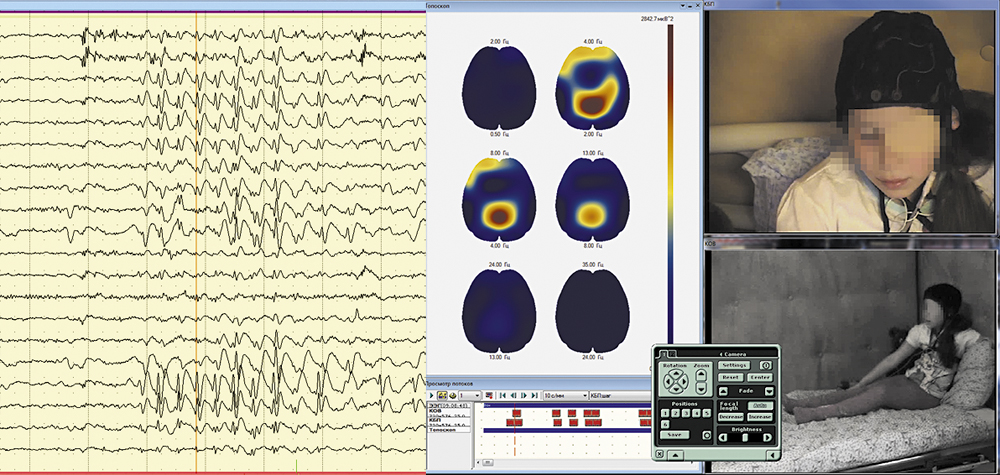

Синхронный просмотр ЭЭГ и видеозаписи при мониторинге или при последующем анализе может проводиться на одном или двух мониторах.

Возможен просмотр видеозаписи с нормальной, ускоренной, или замедленной скоростью, а также режим стоп-кадра и быстрый переход к любому моменту данных ЭЭГ-видеомониторинга (по указанному времени, маркерам или меткам).

Обеспечивается программное управление поворотом и трансфокацией (оптическое или цифровое увеличение – zoom) видеокамер.

В программе сохраняется до 10 типовых настроек поворота камеры и масштаба изображения.

Точность синхронизации ЭЭГ- сигналов с видеоданными при записи и воспроизведении – 1 кадр.

В ходе ЭЭГ-видеомониторинга возможно ручное или автоматическое маркирование различных событий.

Обеспечивается быстрый переход к видеокадру, соответствующему выбранному моменту времени на записи ЭЭГ, и к фрагменту ЭЭГ, соответствующему выбранному видеокадру.

Автоматическое распознавание и маркирование фрагментов нестационарностей или эпилептиформной активности производятся при записи и при обработке ЭЭГ. Найденные фрагменты выделяются цветом, сохраняются и доступны для быстрого поиска.

Для анализа ЭЭГ применяется большинство из общепринятых математических обработок: мощностный и амплитудный спектр, кросс-спектр, функции когерентности, авто- и кросскорреляции с формированием таблиц количественных показателей и их топографическим картированием.